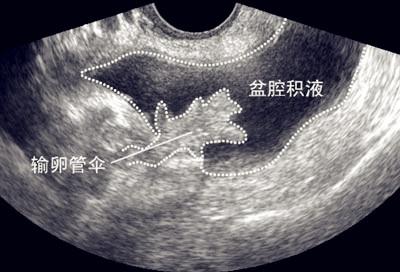

5 .盆腔积液

盆腔积液常见于女性,当盆腹腔脏器有少量渗出液、漏出液或破裂出血时,液体会首先聚积在盆腔,从而形成盆腔积液,月经就有可能导致盆腔积液,按下去有水声,

但盆腔积液可分为生理性盆腔积液和病理性盆腔积液两种。生理学盆腔积液属于正常范畴,病理性盆腔积液可发生在盆腔炎、附件炎或子宫内膜异位症之后,为盆腔炎的主要影像学特征。